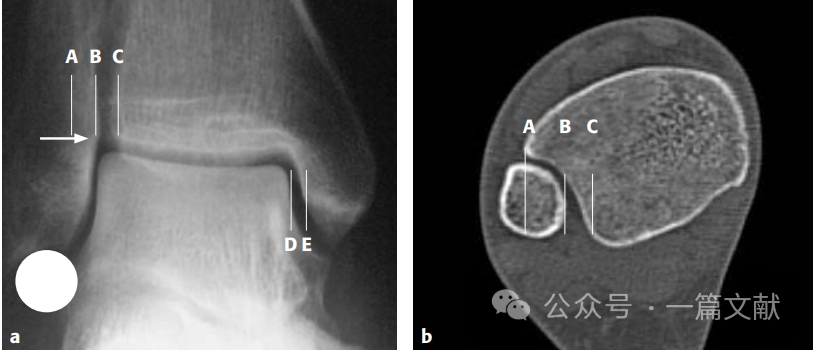

3,透视踝穴位,正常情况下内踝关节间隙DE应小于4mm;胫腓骨外侧间隙BC小于5mm;下图中白色箭头所指的腓骨内侧凸起与胫骨软骨下骨持平,踝穴等宽;图中圆形所示硬币征。